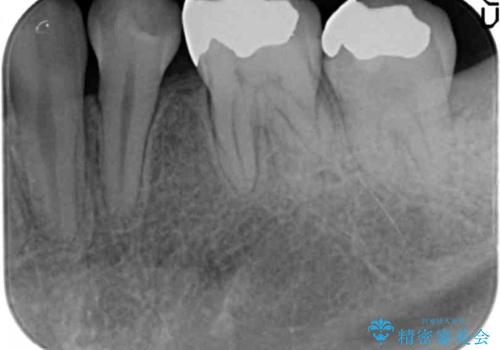

- 矯正治療終了後、前々から気になっていた笑った時に見える銀歯を白くしたいと希望され来院されました。

銀歯を拡大鏡下で丁寧に除去したのち、小さな虫歯も除去し精密で適合の良いセラミックインレーによる再修復を行います。

笑った時に見える銀歯は口元の印象を大きく変えます。矯正治療後のきれいな歯並びに加えて銀歯がなくなったことでより口元の明るい印象になりました。